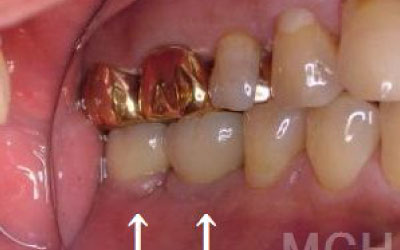

1)ブリッジ

2)歯を大きく削る+支えの歯に1.5倍の力がかかる

3)前後の歯の寿命が著しく減る

ブリッジの支えの歯は、データでは10年以内に68%が抜歯になります。